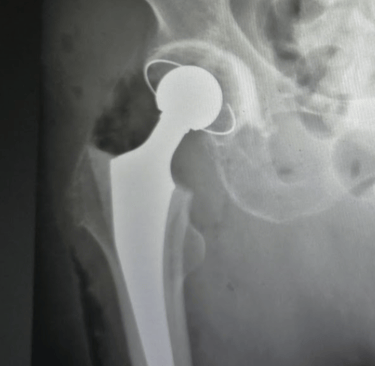

Una prótesis de cadera es un implante que reemplaza la articulación dañada entre el fémur y la pelvis. Está diseñada para imitar la forma y el movimiento de una cadera sana, permitiendo al paciente mejorar su movilidad y el dolor que antes limitaba su vida diaria.

Prótesis total de cadera: Reemplazo completo del acetábulo (cavidad en la pelvis) y de la cabeza femoral.

Hemiartroplastía: Se sustituye solo la cabeza femoral, habitualmente en fracturas específicas en pacientes mayores.